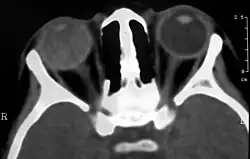

Imaging studies such as ultrasonography (US), Computerized Tomography (CT) and Magnetic Resonance Imaging (MRI) can aid diagnosis. On ultrasound, Coats' disease appears as a hyperechoic mass in the posterior vitreous without posterior acoustic shadowing; vitreous and subretinal hemorrhage may often be observed.[8][9]

On CT, the globe appears hyperdense compared to normal vitreous due to the proteinaceous exudate, which may obliterate the vitreous space in advanced disease. The anterior margin of the subretinal exudate enhances with contrast. Since the retina is fixed posteriorly at the optic disc, this enhancement has a V-shaped configuration.[2]